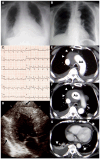

Relapsing pericarditis mimicking aortic dissection